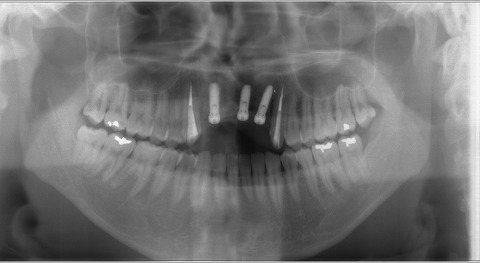

今週もオペを4件行ったのですが、そのうちの2件のオペが、

良く似た前歯に3本のインプラントを埋入するものでした。

決して、同じ部位に同じ本数を埋入するからといって、同じオペと

いうものはなく、昨日(木曜日)の1件は、チタンの網と特殊な膜を用いて

骨を作り、少し鼻腔底にも骨を足して細いインプラントを埋入しました。

また、本日の1件の場合は、特殊な膜のみ用いて骨を作り普通サイズの

インプラントを埋入するものでした。